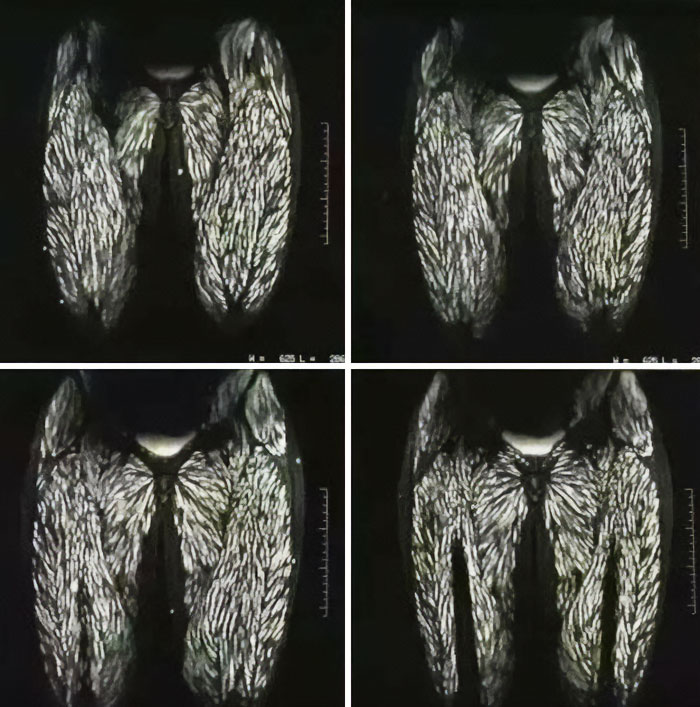

Differences In Muscle Mass

This study looked at how exercise can preserve muscle mass. Here they compare a 74-year old sedentary man and a 70-year old triathlete, and the difference in fat and muscle tissue is extreme